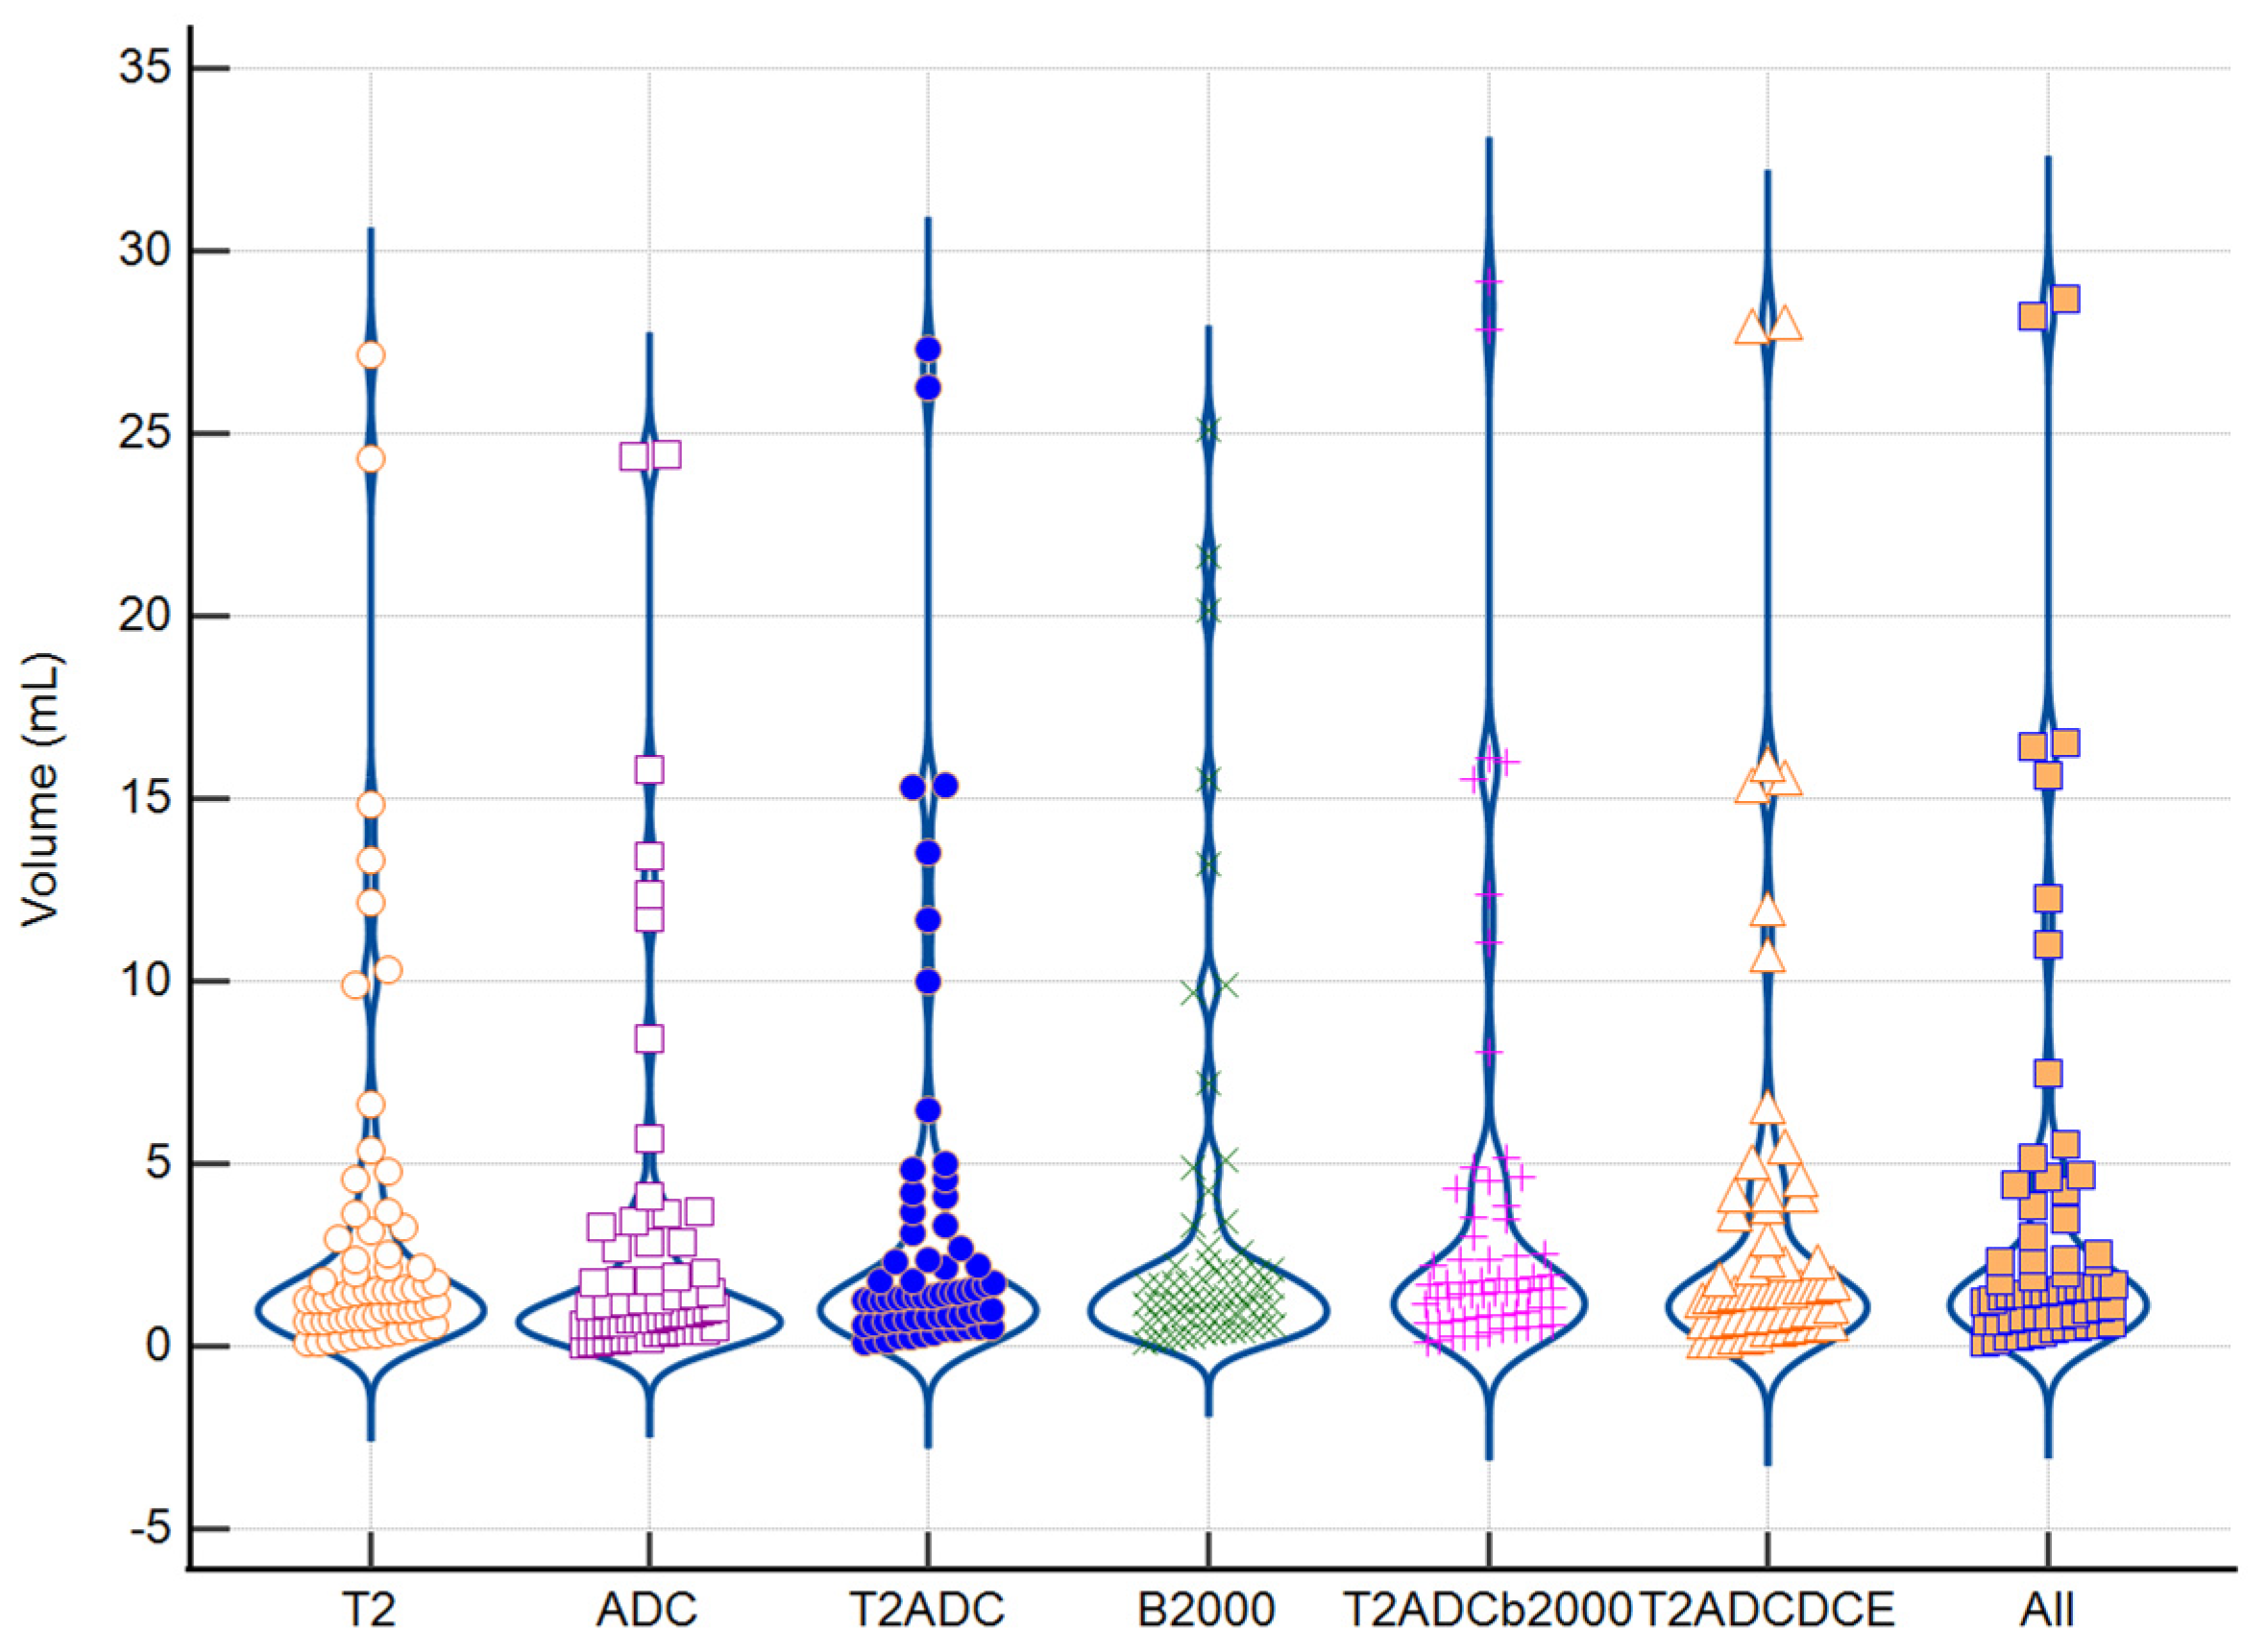

3.4. Impact of Tumoral Volume and PI-RADS Classification